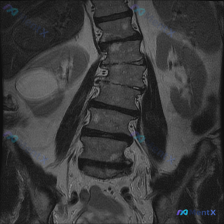

这个腰椎MRI显示左侧凸,更可能是退变还是要警惕肿瘤?

- 腰椎MRI T2冠状位:明显向左侧凸畸形;椎体边缘骨赘形成,部分椎间隙非对称性变窄;凹侧椎间孔区域相对狭窄。

- 额外发现:右侧(图像左侧)肾脏内见边界尚清的明显高信号影。

影像科初步分析里提了“退行性脊柱侧弯”的依据很足,但同时也把“病理性侧弯(肿瘤/骨折)”和“肾细胞癌转移”作为高风险假设放了进来。